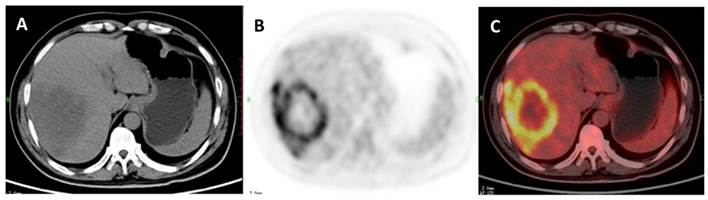

Figure 3

A 47-year-old woman with a liver cyst. A: Axial non-contrast CT-scan showed a cyst-like lesion with low density in right lobe (cross); B: 18FDG PET image showed low-uptake in the cyst (SUVratio=0.3); C: Axial PET/CT fusion image with cross.

The ROC curves and AUC of SUV ratio in younger group are shown in Figure 2. ROC analysis showed that the optimal cut-off value in these patients was 1.17 for SUV ratio and 0.962 for AUC. The younger patients group showed the highest sensitivity and specificity, followed by the older group, and the middle-aged group. Typical 18FDG-PET/CT imaging examples of benign and malignant solitary liver lesions in this group are displayed in Figure 3 and 4. Figure 3 showed a female patient with liver cyst where the SUV ratio was 0.3, and Figure 4 showed a male patient with HCC of which the SUV ratio was 2.1. The ROC curves and AUC of SUV ratio in middle-aged group are shown in Figure 5. ROC analysis showed that the optimal cut-off value in all patients was 1.45 for SUV ratio and 0.650 for AUC. The middle-aged group revealed the lowest sensitivity and specificity. Typical 18FDG-PET/CT imaging examples of benign and malignant solitary liver lesions in this group are displayed in Figure 6 and 7. In Figure 6 from a female patient with liver abscess, the SUV ratio was 4.1, which was much higher than the optimal cut-off value. On the other hand, in figure 7 from a male patient with HCC, the SUV ratio was only 0.98. The ROC curves and AUC of SUV ratio in elderly group are presented in Figure 8. ROC analysis showed that the optimal cut-off value in these patients was 1.25 for SUV ratio and 0.973 for AUC. The elderly group yielded relatively high sensitivity and specificity. Typical 18FDG-PET/CT imaging examples from a patient with benign and malignant solitary liver lesions in this group are demonstrated in Figure 9 and 10, respectively.